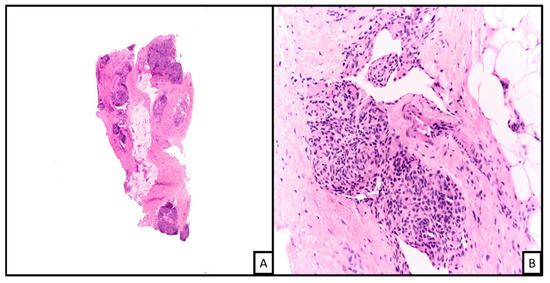

3.6.4. Histologic Features

3.6.5. Ancillary Testing and Immunohistochemical Stains